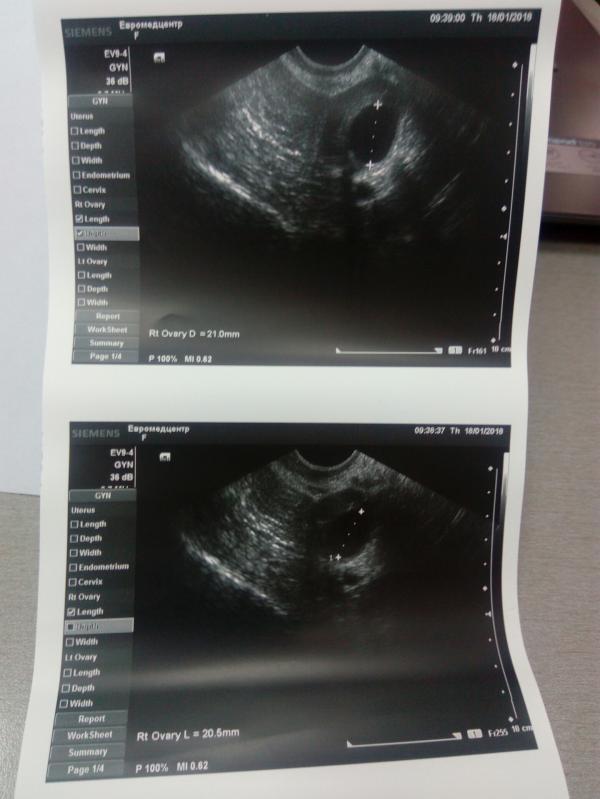

Хочу поделиться своей 3ей стимуляцией, до этого клостилбегитом стимулировались, сейчас Фемарой, и далее андрогель, итог: сегодня 16ый день цикла, овуляции еще не было, так как цикл у меня по 32± дней, созревших два фолликула, 20.5 и 21, мм(на 13день цикла так же было два доминантных по 13.3 и 13.7мм, эндометрий подрос до 8.4мм, был 5.3, в общем ощущение в левом боку потягивает, видимо из-за того, что скоро овуляция! В общем я была бы счастлива если бы произошло зачатие двоих моих фолликов, надеюсь на чудо)))